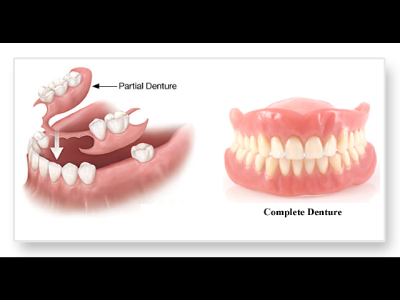

We provide a wide range of dental services which includes Oral Prophylaxis, Tooth Extraction, Tooth Fillings, Veneers, Complete and partial dentures, Crowns, Fixed Bridges, Braces, Retainers, Periodontal/Gum Treatment, Root Canal Treatment, Bleaching/Teeth Whitening, Cosmetic Dentistry, Minor Oral Surgical procedures, and Paediatric Dentistry.